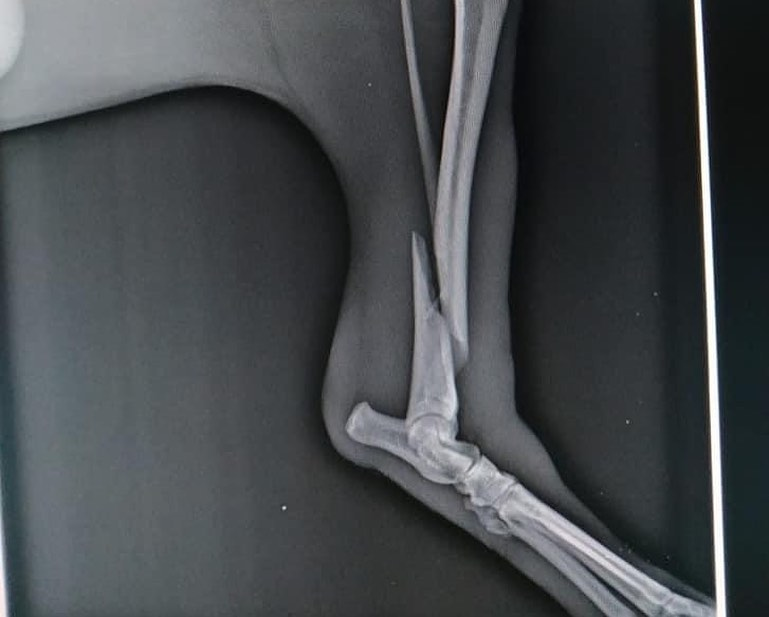

Wir möchten euch Carlos und seine Geschichte vorstellen und hoffen wir bekommen eure Unterstützung. Carlos wurde angefahren aufgefunden und kam in ein Tierheim auf Mallorca. Leider kam es bei einem Unfall zu einem Bruch und zusätzlich hat er beidseitige Knieprobleme. Er muss dringend operiert werden. Wir wurden um Hilfe gebeten, da das Tierheim wo er sich aktuell befindet die Operation nicht leisten kann. Und durch die Ausgangssperre war es bisher noch nicht möglich ihn in eine Spezialklinik zu bringen. Wir möchten Carlos helfen und ihn übernehmen. Wir können ihn nächste Woche in unserer Tierklinik vorstellen und dort kann die Operation durchgeführt werden. Leider sind alle unsere Pflegestellen besetzt und auch auf der Tierschutz Finca bei Mariska ist alles voll besetzt ! Wir benötigen dringend eine Pflegestelle auf Mallorca damit er sich nach seiner Operation erholen kann. Er ist zusätzlich leider total verängstigt und muss erstmals Vertrauen zu Menschen finden. Und leider brauchen wir finanzielle Unterstützung um seine Kosten für die Operation stemmen zu können. Wir starten für diesen Kerl eine Spendenaktion und hoffen so sehr das wir es schaffen. Wie ihr wisst hatten wir in letzter Zeit sehr viele Notfälle dieser Art und nur durch Spenden können wir das überhaupt stemmen. Bitte helft Carlos